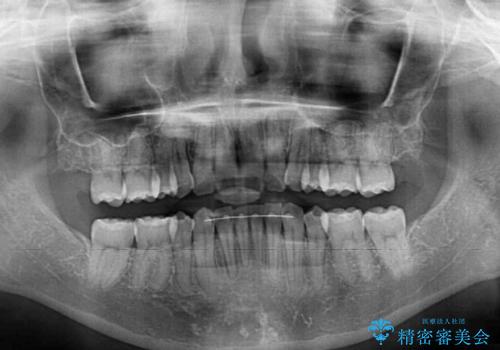

- 以前矯正治療をされていましたが、後戻りが起きたことを気にして来院された患者様です。

全顎的に認められた叢生を改善するため、インビザラインにて治療を行うこととしました。

前歯の叢生の改善を目的として、IPR(歯と歯の間を削る)と歯列全体の後方移動によって歯並びを整えることとしました。

毎日22時間の装着時間を守ってくださいましたが、ハイペースにマウスピースを交換することなく、慎重に治療を進めてくださったので、治療期間はやや長くなりました。

臼歯部も含め、叢生が綺麗に改善され、患者様には大変満足していただきました。